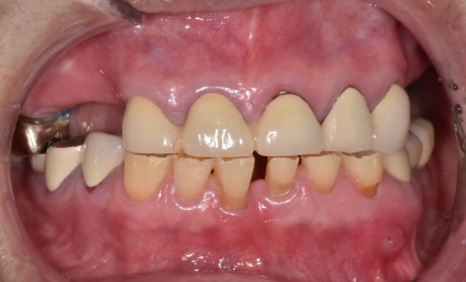

이 환자분은 오랜 시간 동안 치아가 많이 닳아,

전체적으로 치아가 낮아진 상태였습니다.

입안을 보니

앞니뿐 아니라 어금니까지 평평하게 닳아 있었고,

오른쪽 아래 임플란트 보철이

유난히 낮게 제작되어 있었습니다.